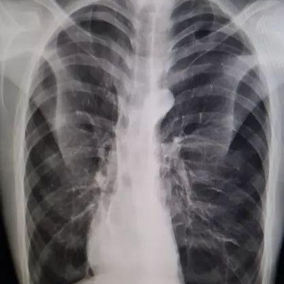

After a preoperative examination, it is observed that the patient's anterior chest wall protruded severely, reaching its peak at the xiphoid process, which presented as a 90-degree angle when viewed from the side. The heart is displaced to the right chest cavity, and the torso is severely deformed, characterized by a broad chest and a noticeably narrowed waist and abdominal area. The narrowing is most pronounced above the pelvis. Moreover, a chest CT scan reveals two large cysts located between the heart and the anterior chest wall in the lower lobe of the left lung, measuring 7x8 cm and 9x10 cm respectively.